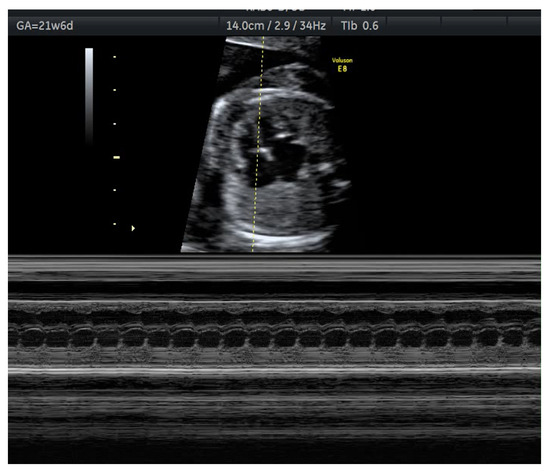

- Veduta, A.; Panaitescu, A.M.; Ciobanu, A.M.; Neculcea, D.; Popescu, M.R.; Peltecu, G.; Cavoretto, P. Treatment of Fetal Arrhythmias. J. Clin. Med. 2021, 10, 2510. [Google Scholar] [CrossRef] [PubMed]